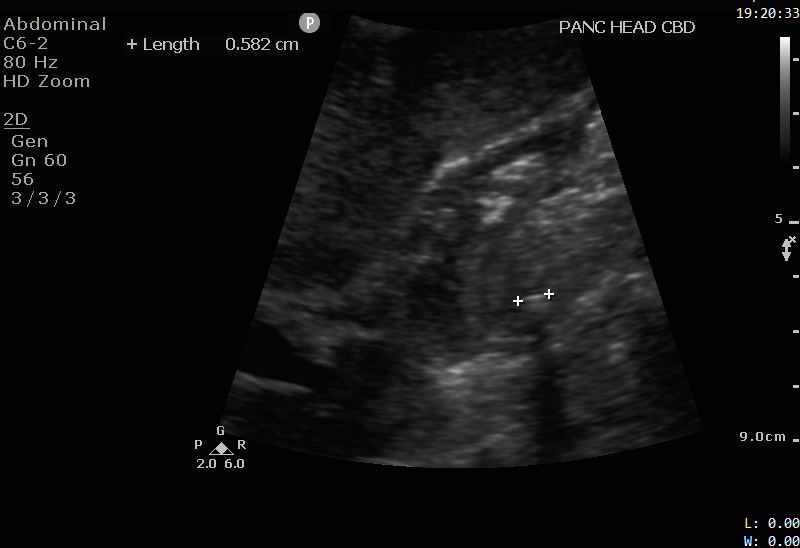

panc-head-stone-2